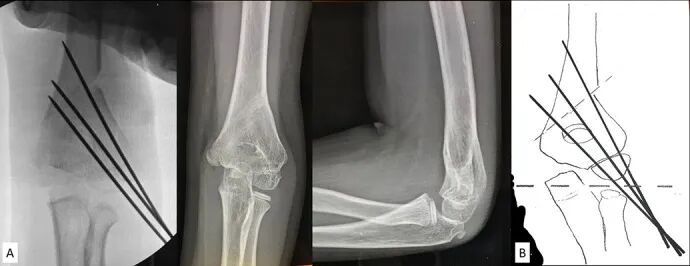

Fig. 2

图 2. 透视影像和示意图展示了逆行克氏针的置入方式。克氏针的位置与走向应事先规划,以便于第三枚克氏针的放置:可以选择放在外侧(图2-A)、位于临时固定的克氏针之间(图2-B),或放在内侧(图2-C和2-D)。病理性关节面在下方以虚线标示。我们更倾向于采用图2-A或图2-B所示的方案。